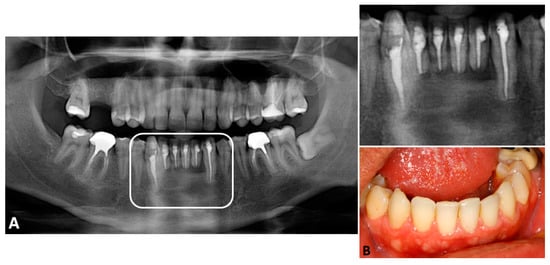

The removal of the lesion was performed under local anesthesia, upon the administration of three anesthetic cartridges of 2% mepivacaine with epinephrine 1:100,000 (Mepiadre, DFL, 1.8 mL, Brazil). An osteotomy was performed in the vestibular cortex to access the lesion (Figure 3A). Following this, after careful curettage, an apicectomy of the involved teeth was performed to access the posterior region of the roots in order to allow a proper peripheral ostectomy at this region of the surgical site. Careful root scaling and planning of the involved teeth were also performed. The closure was done using interrupted sutures (Figure 3B). The entire removed lesion was sent for histopathological examination, which confirmed the diagnosis of GOC.

Considering the high recurrence rates of GOC, adequate follow-up appointments were set. Eight months after the first procedure, a recurrence was detected by CT scan in the lingual portion of the cortical bone (Figure 4A,B). The patient underwent a new surgical approach under local anesthesia. The lesion was accessed through an incision at the lingual region—osteotomy and curettage were then performed, as previously described (Figure 4C).

Figure 3. Trans-operative images of the surgical procedure. (A)—First surgery—the surgical access and the ostectomy were performed via vestibular cortex. (B)—Surgical flap was positioned, and sutures were performed.

Figure 4. (A)—Representative coronal cut and (B)—sagittal cuts of the CT scan 8 months after the first surgery, revealing recurrent lesions in the apical region, lingually. (C)—Trans-operative image of the second surgical approach, aiming the removal of the recurrent lesion in the lingual portion of the cortex. The arrows point to the recurrent lesions.